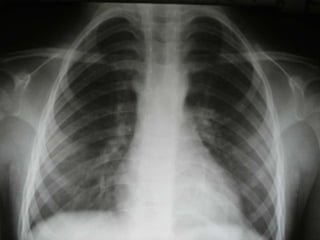

Criterios Radiológicos

• Permite evidenciar la presencia,

extensión y localización de la lesión en

pacientes con sospecha de TB

• En la Tb miliar puede hacer el

diagnóstico

• Es de mucha ayuda en el derrame

pleural tuberculoso

• La tuberculosis extrapulmonar tiene

radiografías de tórax normal

• Edad: 1 año 9 meses

• Tos desde hace 1 año

• Diaforesis

• Falta de apetito

• Ex físico: normal

• Multiples tratamientos

• Peso al inicio: 9 Kg

• Peso a los 2 meses: 12

Kg